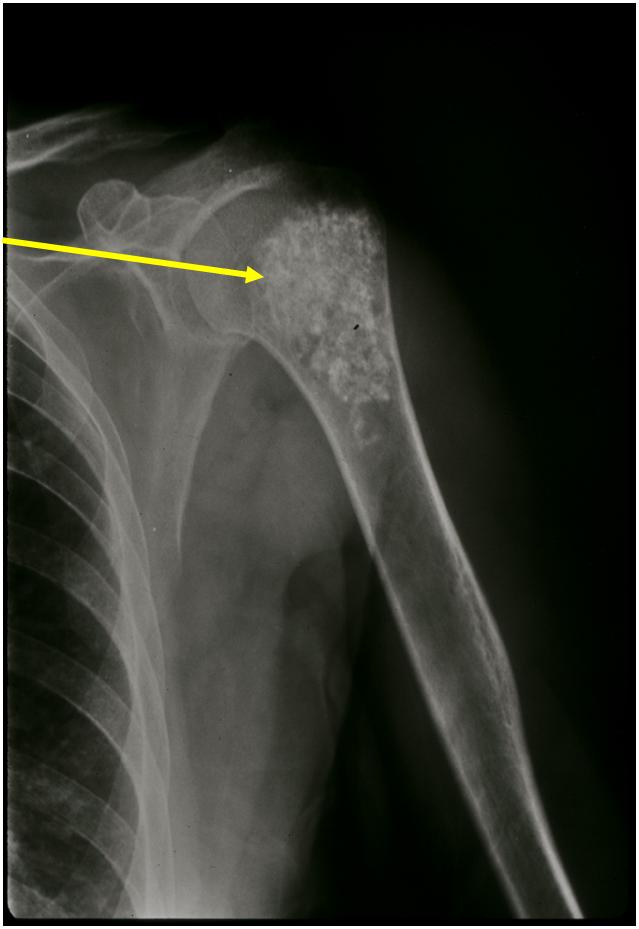

Ring and Arc Calcifications Minimal Endosteal Scalloping Cortex Intact No Soft Tissue Component No Periosteal Reaction

Ring and Arc Calcification No Endosteal Scalloping

Metaphyseal Tumor Heavy Calcifications Ring and Arc Pattern of Calcifications Minimal Endosteal Scalloping No Cortical Destruction No Periosteal Reaction No Cortical Destruction No Soft Tissue Component